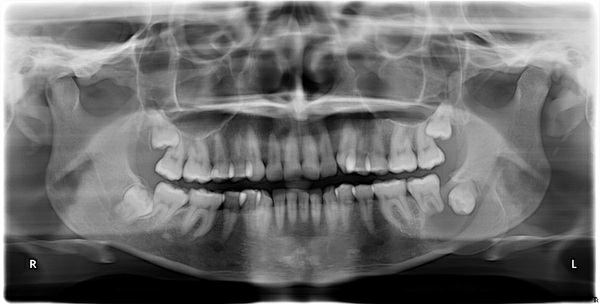

2. (Select ONE OR MORE correct answers)

The radiograph shows evidence of